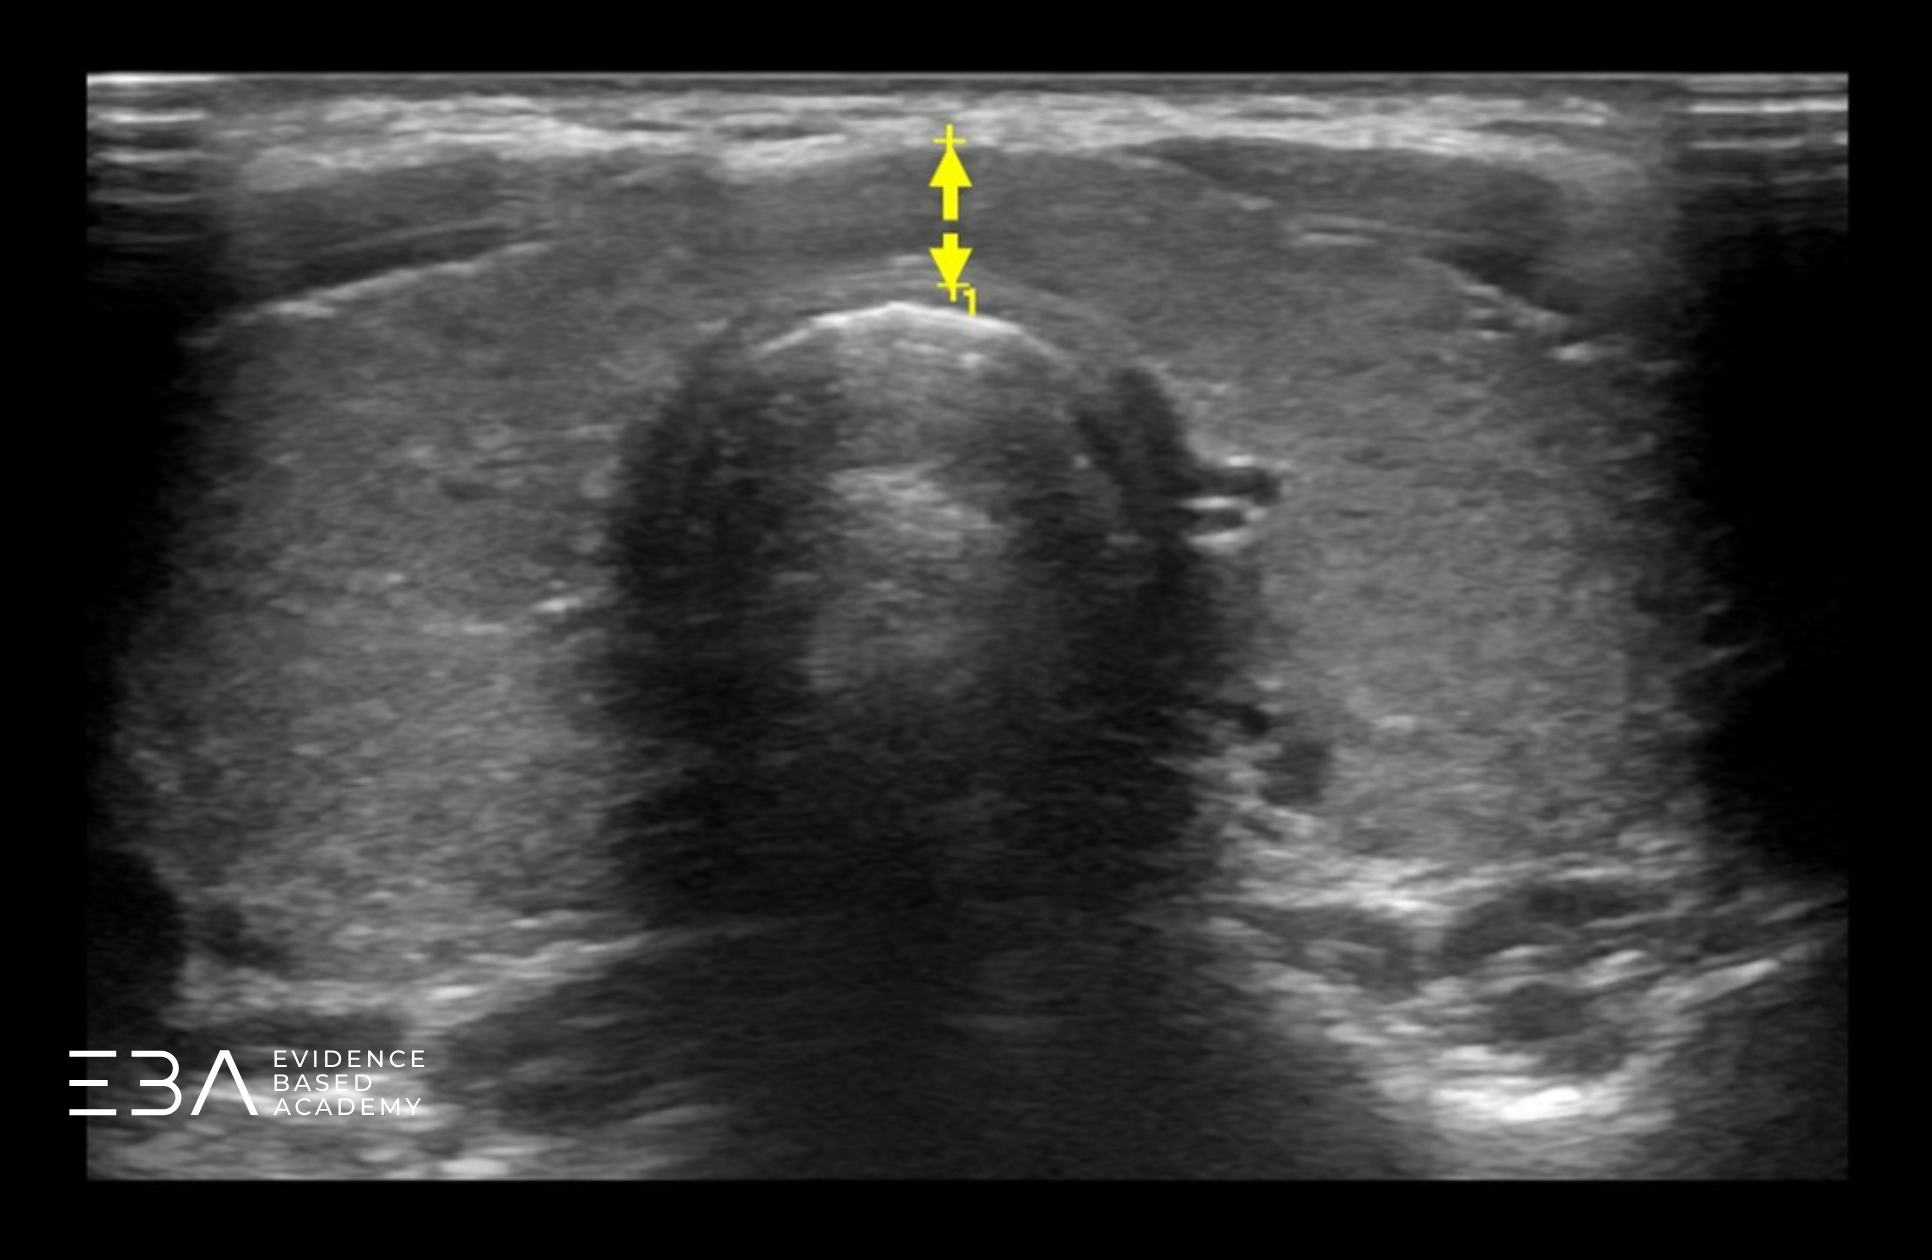

Pomiar cieśni

Wymiar przednio-tylny (AP) cieśni uzyskujemy w przekroju poprzecznym, w miejscu, gdzie cieśń jest najgrubsza. Jest to jedyny wymiar cieśni, który oceniamy.

Pomiary grubości cieśni.